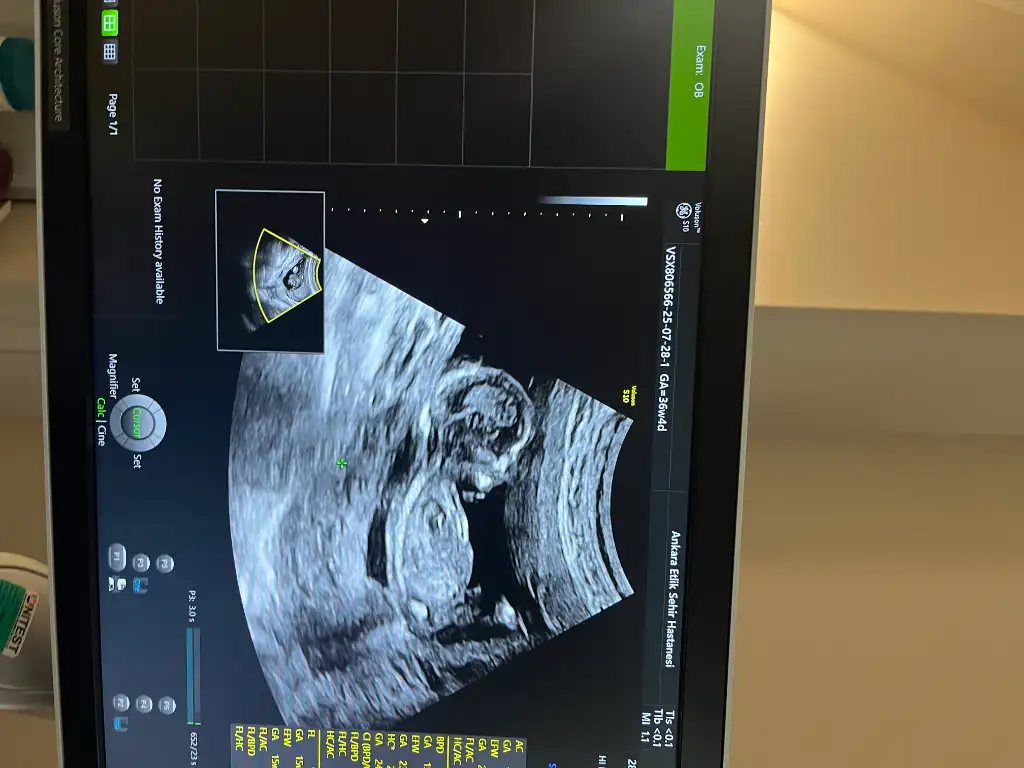

Bu attığınız ultrasondaki bebek 36 hafta 4 gün yazıyor amaKızlar yarın cinsiyeti öğreniyorum tahminde bulunurmusunuz ?

Kız ne 36 haftası 15 haftalıkBu attığınız ultrasondaki bebek 36 hafta 4 gün yazıyor ama

Bak kız sol üstte ne yazıyor? 36w4d 36 hafta 4 günlük demek. Yanlış fotoğraf mı koydun?Kız ne 36 haftası 15 haftalık

Kesinlikle size katiliyorum. Bu 15 haftalik bebek resmi degil. Ve yukarida GA (Gestational age) 36w4d yani 36 hafta 4 gunluk yazulmis:)Bak kız sol üstte ne yazıyor? 36w4d 36 hafta 4 günlük demek. Yanlış fotoğraf mı koydun?